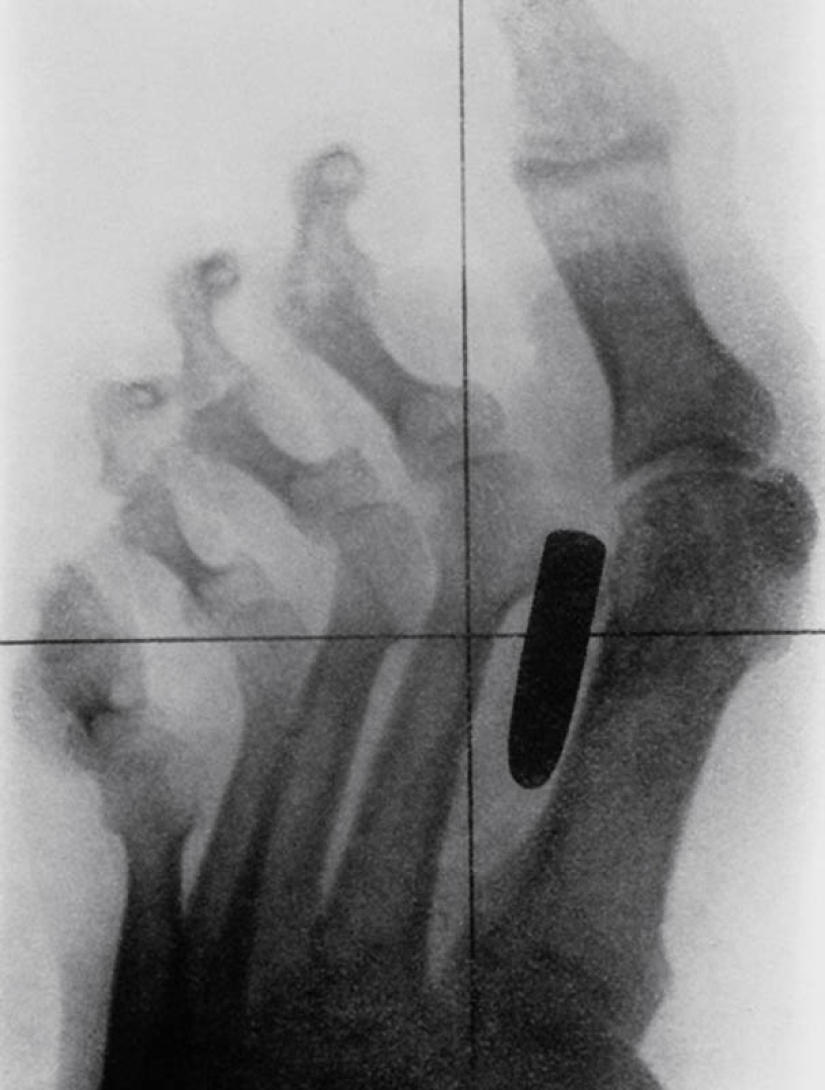

3. Antigua imagen de rayos X del pie de un soldado de la Guerra Anglo-Bóer (1899-1902) con una herida de bala. La bala se alojó en el hueso metatarsiano entre el pulgar y el segundo dedo.